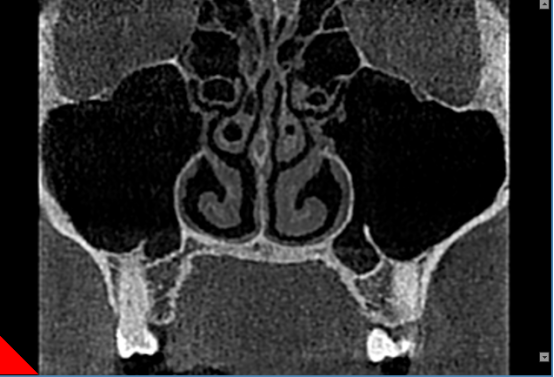

窦部扫描提供窦部综合性判断。